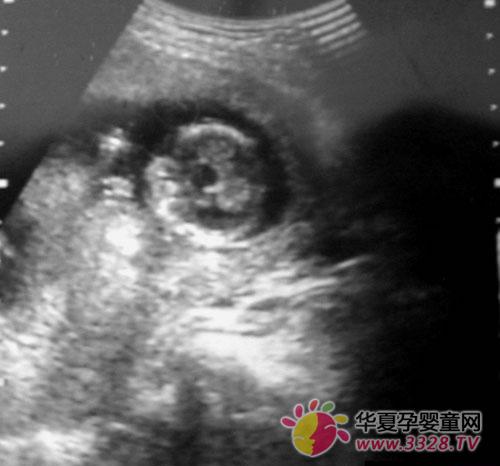

怀孕两个月胎儿图

胎儿发育全过程图